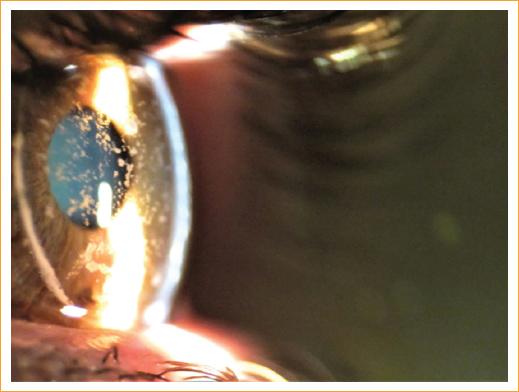

Mujer de 22 años que refiere deslumbramiento y disminución de la agudeza visual sin mejoría con anteojos o lentes de contacto. Se le diagnosticó distrofia granular corneal y se sometió a queratoplastia penetrante (QPP) en ambos ojos. El procedimiento se realizó sin complicaciones. Después de 12 años de seguimiento (cuando tenía 34 años) regresó refiriendo los mismos síntomas: deslumbramiento y baja agudeza visual en ambos ojos. El examen con lámpara de hendidura mostró los injertos de córnea con opacidades granulares parduscas que afectaban al estroma anterior en la córnea central (Fig. 1). Este caso ilustra la recurrencia de la distrofia granular en injertos de córnea.

Figura 1 Injerto de córnea con opacidades estromales rodeadas de córnea clara y sana, lo que indica la recurrencia de la distrofia granular corneal. Nótese una línea densa, blanca y circular que representa el límite entre el injerto de córnea y la córnea receptora.